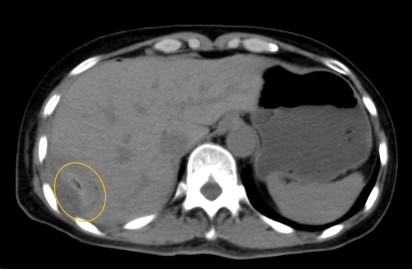

入院后,影像診療中心立即給李女士完善了CT和MR檢查,發(fā)現病變位于肝包膜下,臨近膈肌,消融治療過程中有并發(fā)損傷膈肌的可能,難度較大,但是采用精準影像定位是可以完成的。陳寶瑩主任立即與腫瘤三病區(qū)劉金鵬主任聯系,并與影像微創(chuàng)治療小組進行MDT討論:患者為卵巢癌肝右葉包膜下單發(fā)轉移瘤,最長徑不超過3cm,患者對局部治療的主觀愿望強烈,符合消融治療專家共識,遂制定了影像引導下局部消融治療聯合全身治療的綜合治療方案。

針對這個特殊部位的腫瘤,要想消融完全,那么膈肌損傷的風險就很高,陳寶瑩主任帶領影像微創(chuàng)亞專業(yè)組成員仔細閱讀CT圖像,設計進針路徑,結合MR圖像確定腫瘤活性范圍,制定了周密而詳盡的消融計劃。臘月二十九,即住院第二天影像微創(chuàng)治療小組圓滿為患者完成了腫瘤微波消融治療,觀察24小時后出院回家過年。術后48小時隨訪患者無明顯不適,術后7天隨訪,患者肝功、血常規(guī)等各項指標均恢復正常。